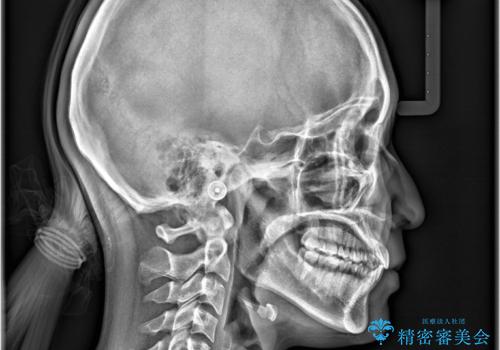

精密矯正検査を行った結果、歯を抜かずに行う、非抜歯のワイヤー矯正で治療を行う方針となりました。

歯並びの乱れに加え、**反対咬合(上下のかみ合わせのズレ)**も認められたため、見た目だけでなく、かみ合わせの改善も同時に行っています。